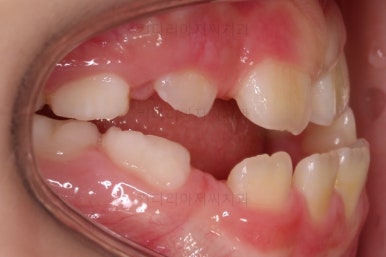

초진 시 입안의 모습입니다.

아래쪽 치열이 전반적으로 윗니보다 앞쪽에 위치한 전형적인 앵글씨 3급 부정교합인데요.

어금니에서부터 앞니까지 아랫니가 윗니보다 앞쪽에 위치하네요.

특히 앞니는 아랫니가 윗니보다 나와있는 "반대교합" 상태였고요.

또한 위아래로 겹침이 없고 떠있는 "개방교합" 상태였어요.

즉, 앵글씨 3급 부정교합 - 반대교합 - 개방교합 등 굉장히 복합적인 교합의 문제를 가진 환자였습니다.